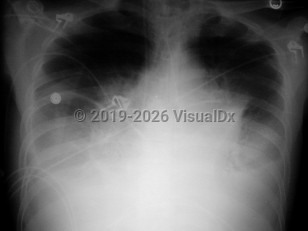

Pleuritic chest pain, Leg pain, Dyspnea, Developed acutely , History of Chronic obstructive pulmonary disease, History of Pulmonary hypertension, Tachycardia, Unilateral leg edema, Sinus tachycardia, S1Q3T3 pattern, T wave inversion, Pathologic Q waves, 70-79 year old Female

Acute respiratory distress syndromeAcute respiratory distress syndrome

Acute eosinophilic pneumoniaAcute eosinophilic pneumonia